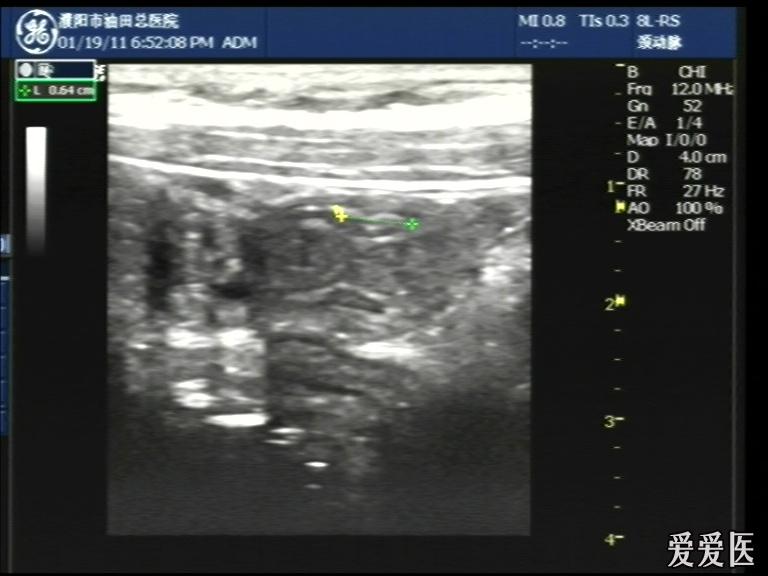

晚6点半,儿童、腹痛5日,无明显压痛及反跳痛。

超声检查:于下腹部可见“双环征象”,双环重叠长约6mm,检查期间观察可见肠蠕动;CDFI:未见明显异常血流信号。

超声提示:下腹部双环征,考虑肠套叠可能,请结合临床